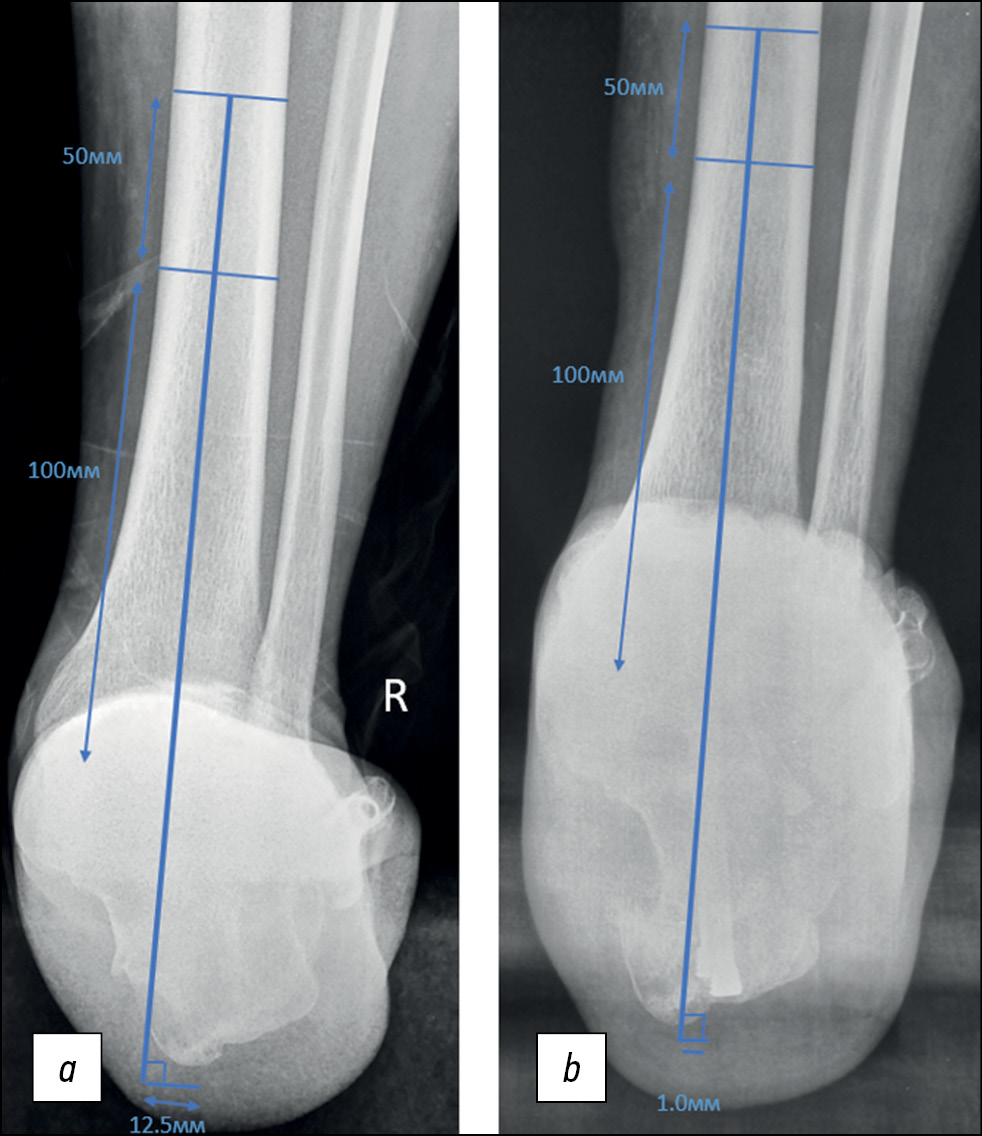

Рентгенологическая оценка

Для определения рентгенологически измеряемого результата послеоперационной коррекции оси пяточной кости мы использовали методику, ранее описанную Saltzman и el-Khoury [24]. Подводя итог, можно сказать, что hindfoot moment arm, или направление смещения (положения) оси пяточной кости, определяется как кратчайшее расстояние между осью большеберцовой кости и наиболее дистальной точкой пяточной кости (рис. 1, a и b).

Рис. 1. (a) До- и (b) послеоперационный снимок. Результат коррекции оси заднего отдела стопы (hindfoot moment arm) Измерения на рентгенограммах, выполненных в проекции Зальцмана, определяются как кратчайшее расстояние от средней оси большеберцовой кости до самого дистального аспекта пяточной кости.

Fig. 1. (a) Before and (b) postoperative X-ray. The result of hindfoot moment arm correction. Measurements on radiographs taken in the Saltzman projection are defined as the shortest distance from the medial axis of the tibia to the most distal aspect of the calcaneus.

Вышеописанное измерение было выбрано на основании надёжности метода, многократно подтверждённой изученными нами научными работами. Все рентгенограммы были сделаны спустя 24 нед с момента операции.